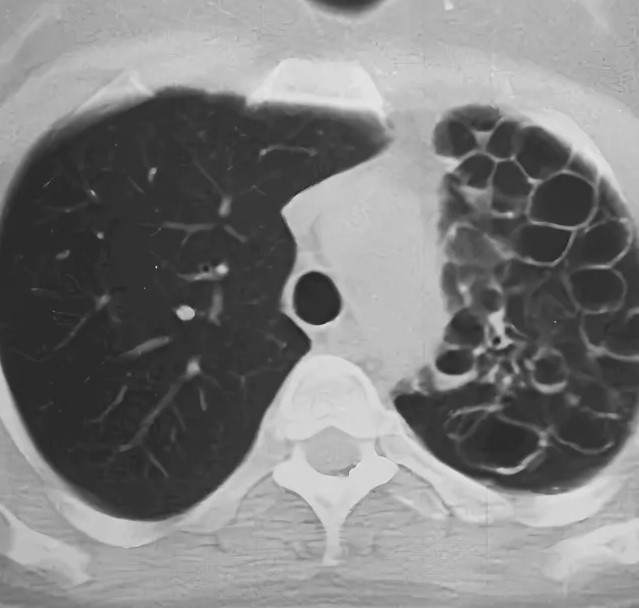

Кт легких детям

Кт легких детям 105 фотографий